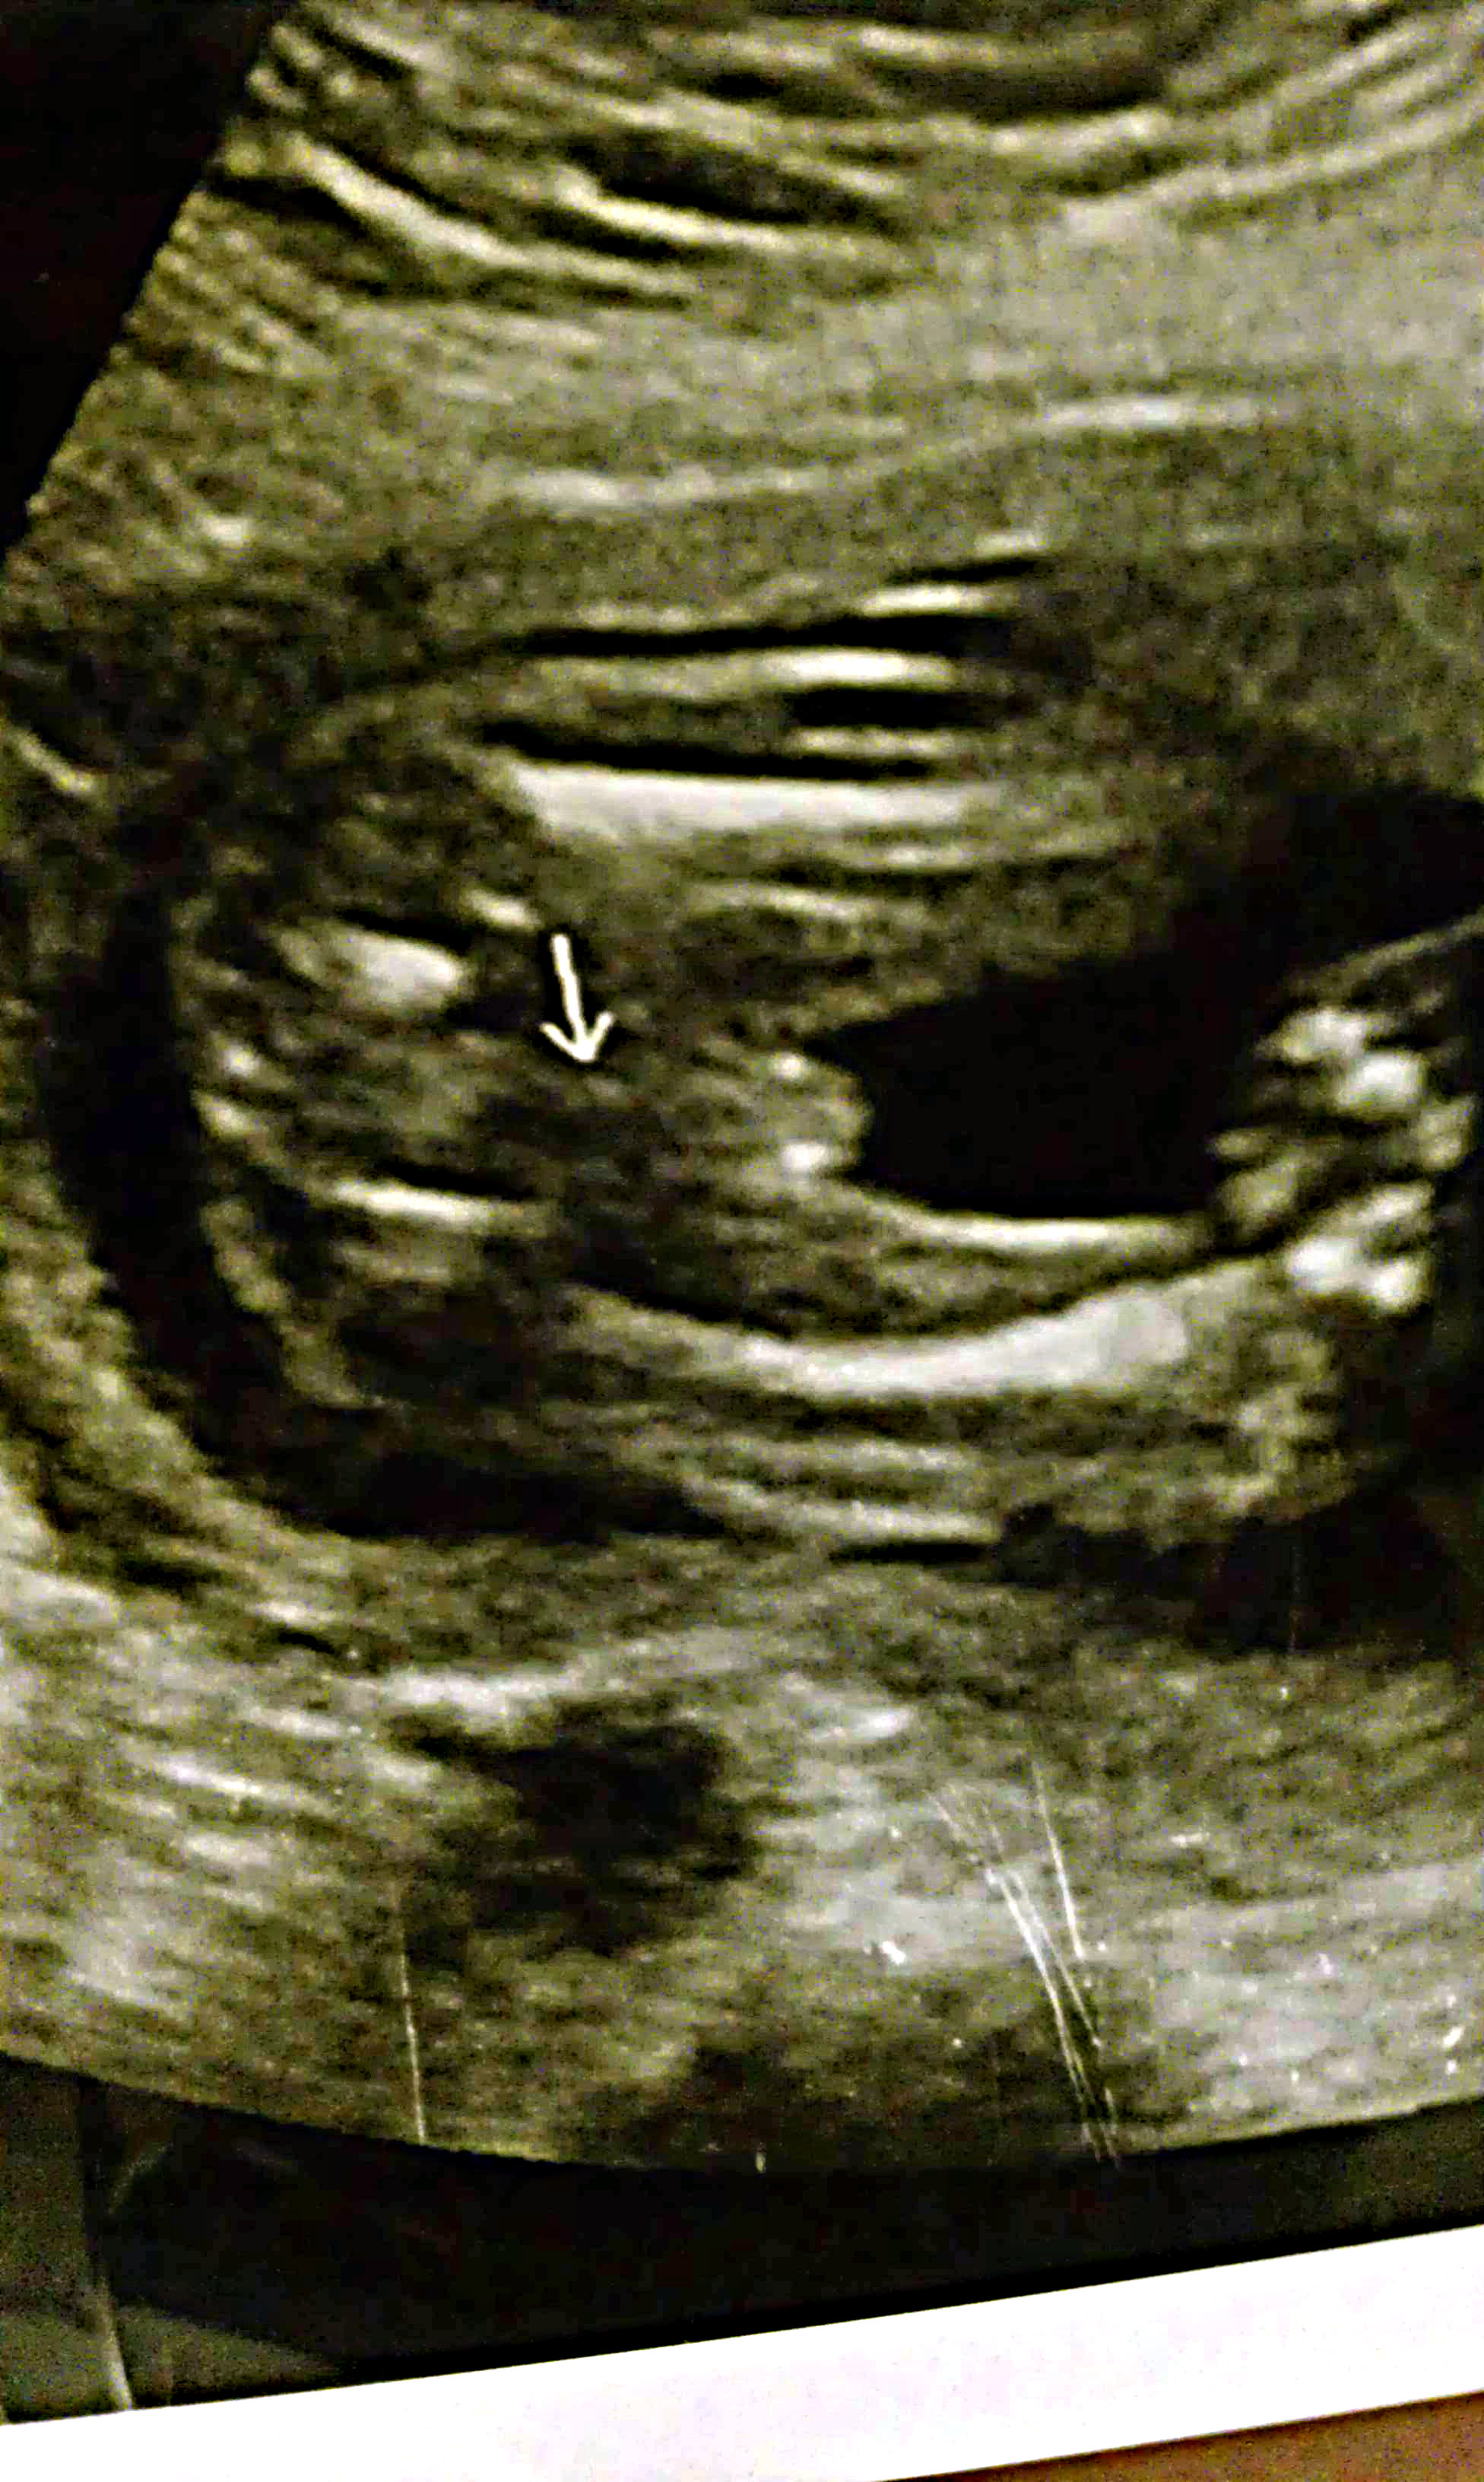

New to this site, tried to get a better picture of our 19-20 week ultrasound. The tech was inexperienced (she actually asked if I could come in sometime so she could practice). She immediately said boy, but didn't spend more time looking than it took to type the letters. I had an ultrasound at around 26 weeks or so and my doctor said it "might be a boy", that he couldn't really tell.. Then had a 3D done at 30 weeks and the tech said she couldn't tell the gender for sure. I've compared this US to my son's US from 5 years ago, and his was a definite "turtle" shot. I've read/seen US of girl's being swollen and protruding out some... would that happen at 19-20 weeks, though?

What's the arrow pointing to on the second image?

There it is! It looks like a clear boy to me!